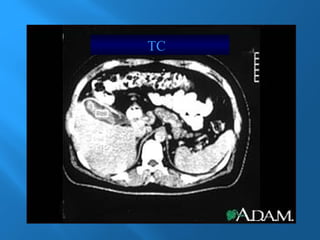

2.- TC

TAC

TC